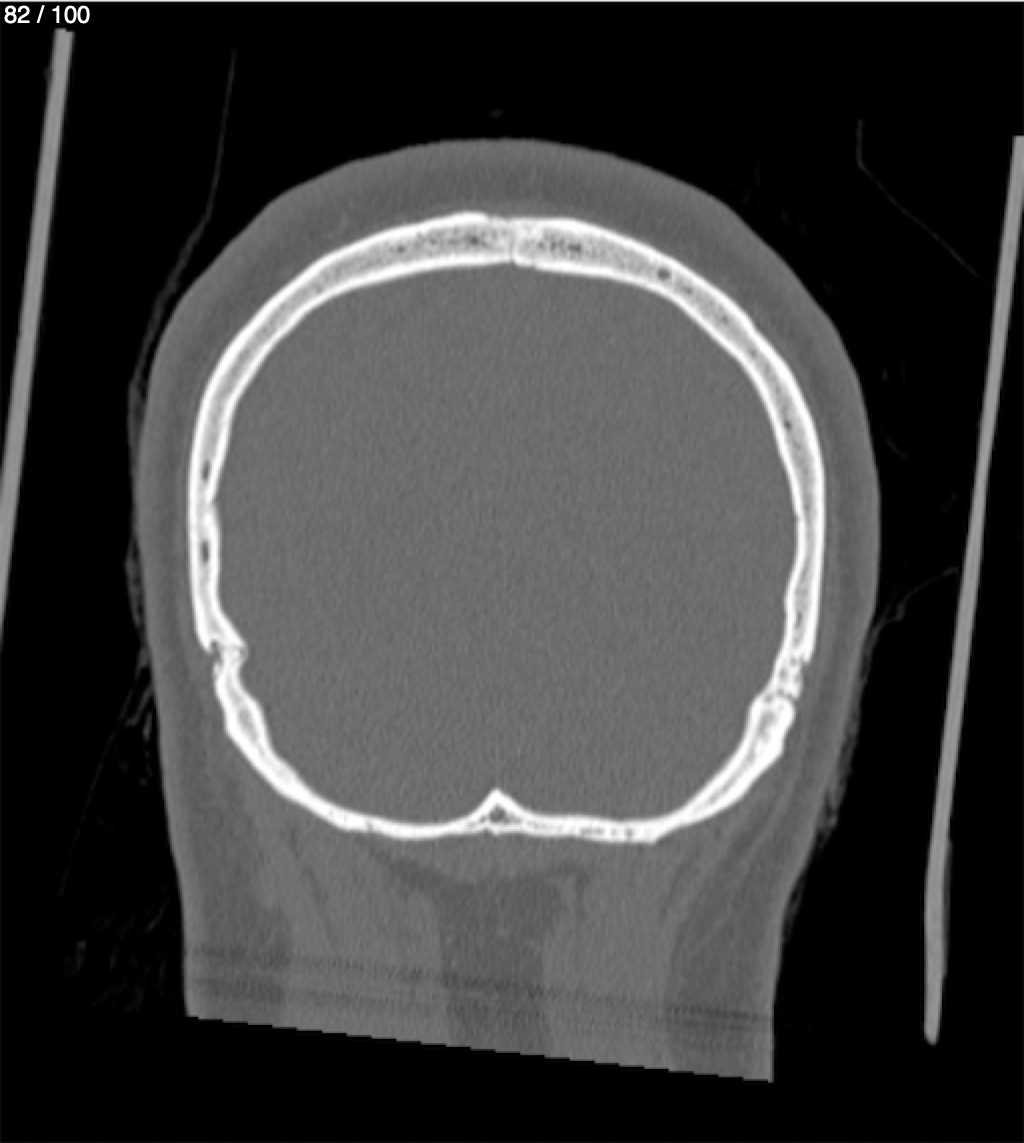

Reybet Garcia Fuentes 30A - T.C Craneo